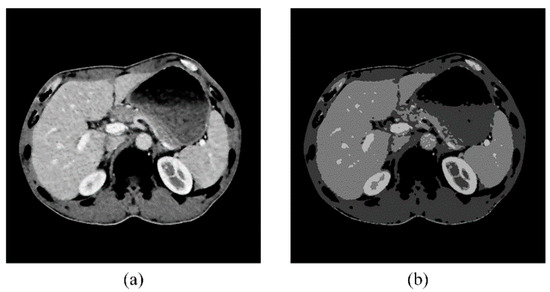

The final set of peaks was obtained after collecting the peaks of all the volume histograms, such that they are used as the K-mean centers for the entire abdominal CT sequence. The clustering process utilizes the Euclidean distance as the similarity measurement and the resulting clustering is depicted in Figure 4. Our adaptive clustering algorithm ensures that the kidneys are always assigned to the brightest cluster, thanks to the preprocessing step that removes the spine and ribs.

Figure 4. Cluster result based on multi-region volume histograms. (a) Original abdominal CT image. (b) Cluster result.